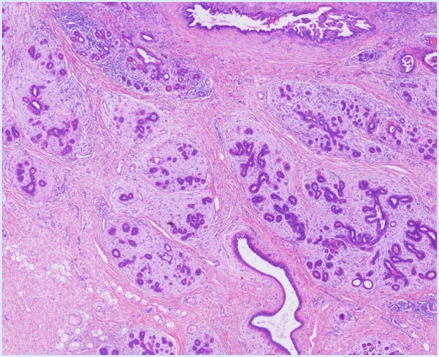

High Image Quality for Digital Pathology

KFBIO Digital Pathology Slide Scanner (PRO) is a world leader in the accuracy of movement, focus, and image processing, and its accurate whole slide imaging not only meets the requirements of digital slide viewing and operation but is also suitable for AI-assisted image analysis.

High Quality, 3 Colors Independent Processing

K-SCP color processing method helps restore the original color, saturation, color temperature, color contrast and other indicators to enhance images, as well as color compensation of different displays after imaging.

High Resolution, 0.5µm/pixel (20X), 0.25µm/pixel (40X)

It adopts top optical accessories. The light source, objective lens, camera, optical path and other accessories are comprehensively optimized. It greatly improves the optical resolution to directly observe the structure and details in the cell. The nucleus edge is sharp and the internal structure is clearly visible. The resolution distance can be as small as 0.125µm.

High Precision, 20nm Fine Control, 80x magnification

Linear magnetic axis drive and grating ruler positioning mechanism are adopted to achieve ultra-high precision of image movement control and image positioning at the nanometer level. It helps sample fast and accurately to achieve stable imaging for a longer period of time. The magnification can reach 80x.